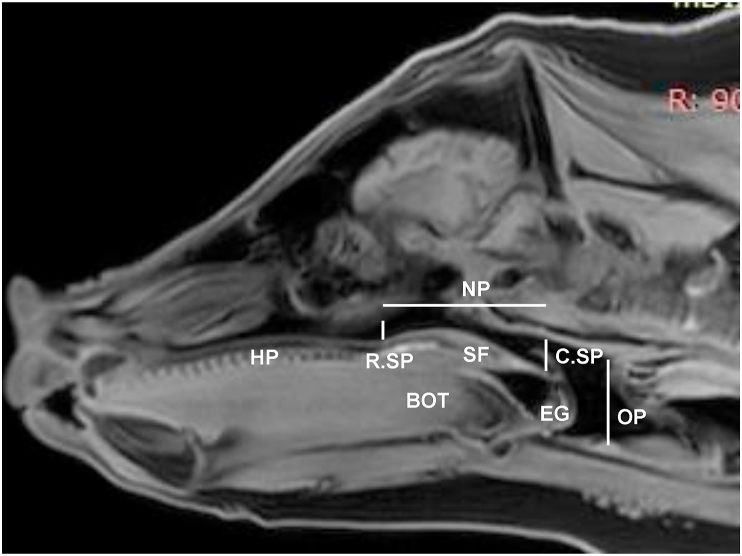

Figure 3.

VISTA MRI sagittal slice by RadiAnt DICOM Viewer to measure dimensions of nasal and oral pharyngeal airway spaces. HP: Hard palate; SF: Soft palate; BOT: Base of the tongue; EG: Epiglottis. Two vertical lines indicate the rostral and caudal ends of soft palate (R.SP and C.SP). Horizontal and vertical dotted lines indicate the locations of nasal and oral pharyngeal airway spaces (NP and OP), respectively.